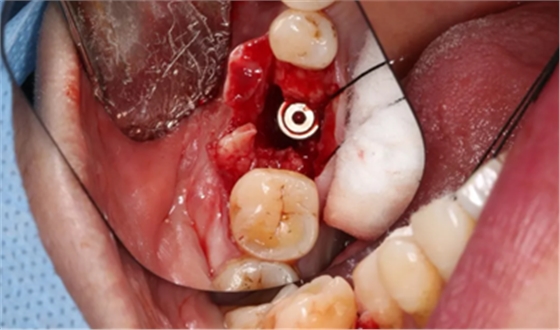

14、植骨手术过程

刮除肉芽组织及种植体表面清洁后,种植体唇侧骨缺损区植入人工骨粉。

(摄于2017年8月10日)

引导骨再生

无张力间断缝合切口。